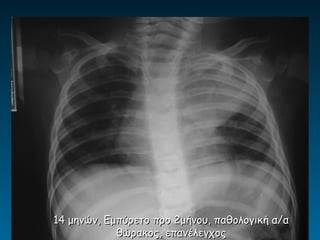

14 μηνών, Εμπύρετο προ 2μήνου, παθολογική α/α

θώρακος, επανέλεγχος